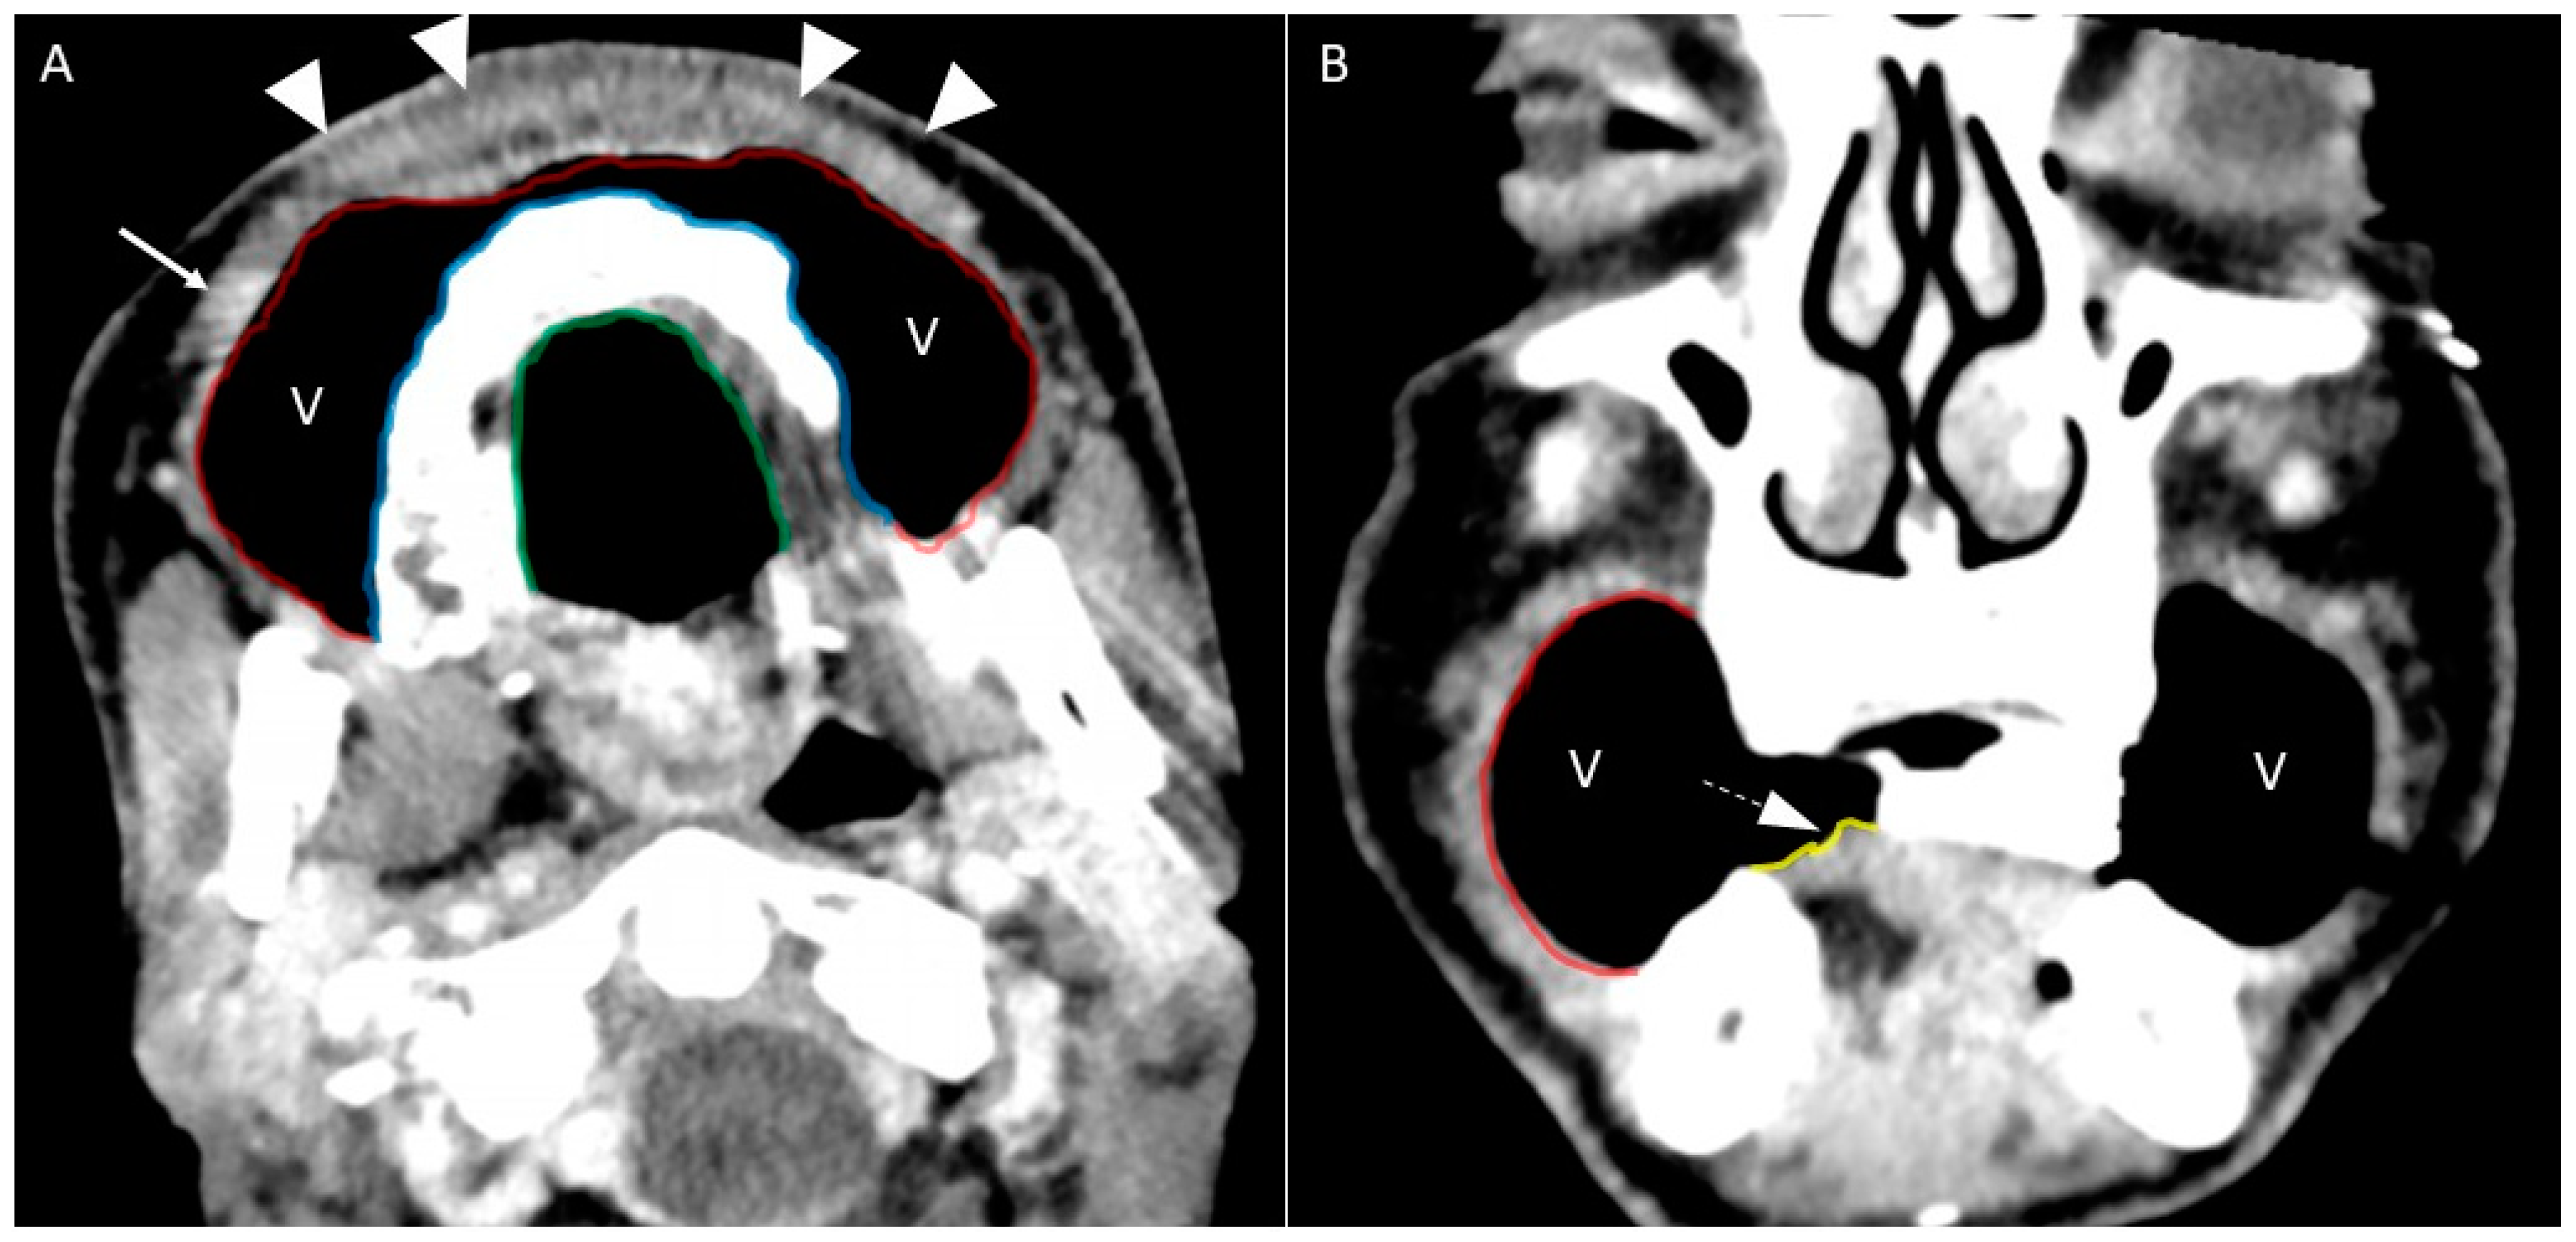

- Puffed cheek technique. The vestibule of the mouth is a virtual cavity due to the contact between the mucosa of the lip, cheek, and gingiva. Puffed cheek technique helps to determine if the lesion is arising from the buccal, gingival, or lingual mucosal surface since patients blow uniformly through pursed lips and the mucosal surfaces appear separated from each other. Therefore, the vestibular cavity can be appreciated as an air-filled horse-shoe-shaped space both on MSCT and MRI (Figure 10 and Figure 11).